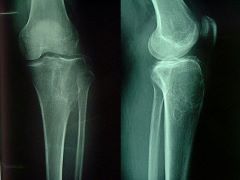

骨巨细胞瘤的病因有哪些!骨巨细胞瘤是一种由增殖性单核细胞和破骨细胞样多核巨细胞构成的具有局部复发倾向的侵袭性原发良性骨肿瘤。那么骨巨细胞瘤都有什么病因,怎么会得骨巨细胞瘤病因呢?现代医学对于骨巨细胞瘤的病因目前还不很清楚。组织循环丰富,质软而脆性大,似肉芽组织,易出血,有纤维机化区及出血区。

骨巨细胞瘤病因按良性和恶性程度分为三度,以下对骨巨细胞瘤病因做详细阐述:

一度:约有一半的巨细胞瘤属于此类,为明显良性,巨细胞很多,少有细胞分裂,注意需全部肿瘤都是一度才能判断为一度肿瘤。

二度:恶性或良性不易区别,间质细胞较多,巨细胞较一度为少。

三度:为明显恶性,发生较少,间质细胞多,细胞核大,形态如肉瘤,细胞分裂多。巨细胞较少而小,核数目亦少,一、二度可转化为三度。